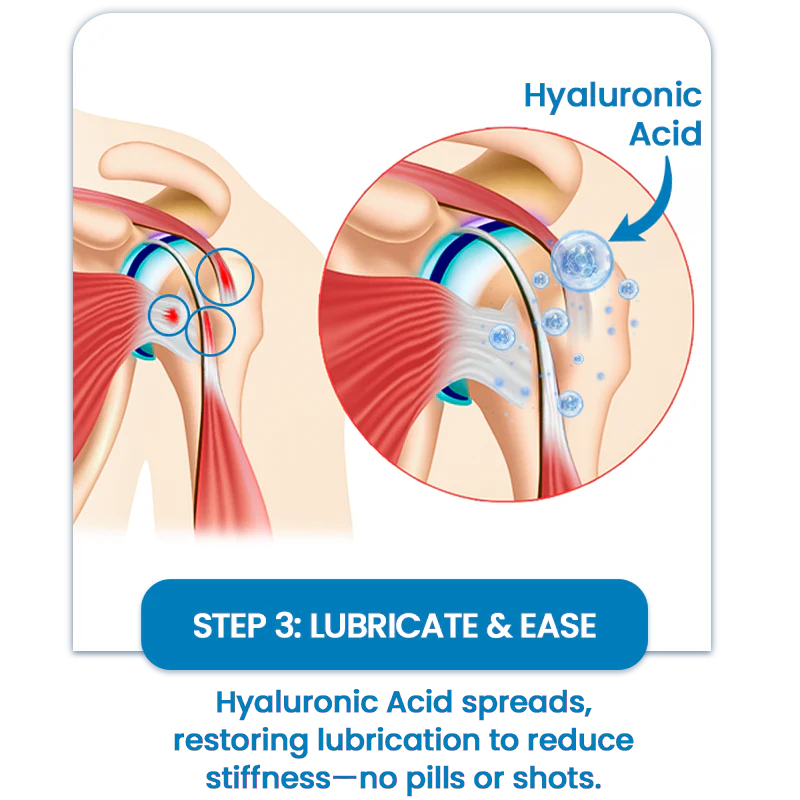

How It Works-Three-Step Joint Relief

Hyaluronic Acid

Restores lubrication, eases friction

✓ LUBRICATION